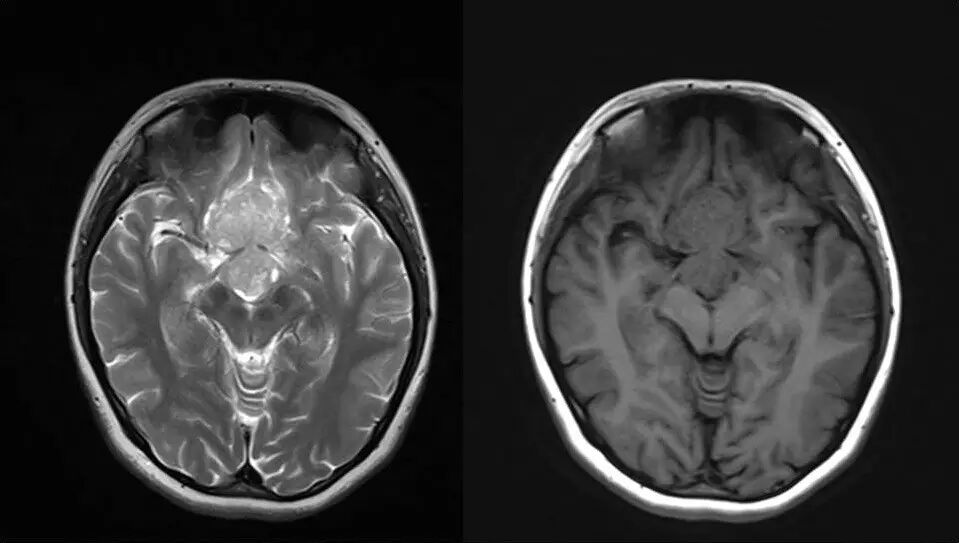

2.MR检查显示肿瘤位于鞍区,分叶状生长,呈稍长T2、稍长T1异常信号影,边界清楚,内部信号不均匀,其内可见“微囊”状异常信号影,视交叉受压上抬,DWI呈等或略高信号影,注药后呈不均匀明显强化;